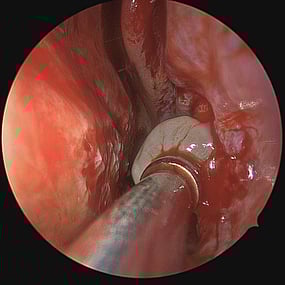

Sino-Nasal Polyps

Sino-Nasal Polyps are non-cancerous growths that develop in the lining of the nose or sinuses. They can obstruct the nasal passages and sinuses, leading to symptoms similar to chronic sinusitis such as nasal congestion, facial pressure, and reduced sense of smell.